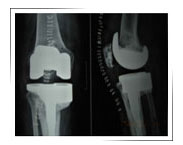

After Surgery

After Surgery X-ray

Function After Surgery